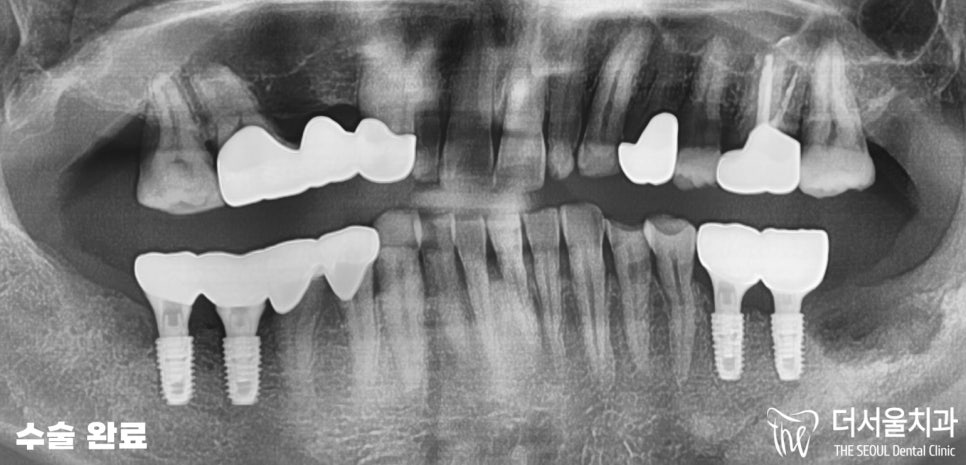

양쪽 아래 어금니 부분에

픽스처를 식립이 잘 이뤄졌습니다.

물론 픽스처를 식립하면서

윗니 크라운 보철 치료를

함께 진행해줬죠.

10번대는 브릿지를,

24번 파절된 치아 는 크라운,

26번은 교합을 위해 보철 치료 를

수정구치과 에서 해드렸습니다.

이후 뼈와 고정체의 결합이

잘 이뤄지기를 기다린 뒤,

상부 보철물 세팅을 해드렸습니다.

『결과』

👉어금니 발치 후 임플란트,

크라운 보철 등

다수의 치료 가 끝났습니다.

수정구치과 에

처음 내원하셨을 당시

모습과 비교했을 때,

많이 개선된 것을 볼 수 있습니다.

파노라마로 체크했을 때도

안정감있게 뼈와 잘 고정되었으며,

크게 비틀어졌던 교합 역시

올바른 형태로 진행될 수 있게끔

개선된 것을 볼 수 있습니다.